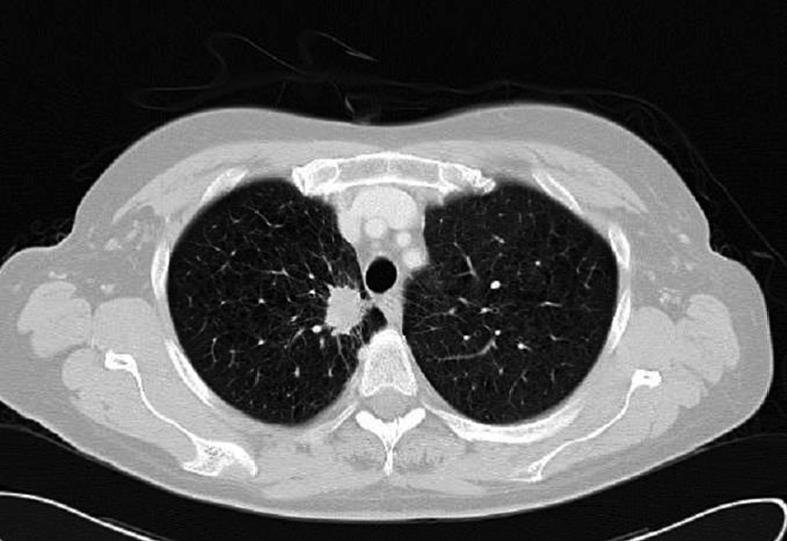

Figura 2. TAC torácico que demuestra nódulo pulmonar espiculado en segmento apical del lóbulo superior derecho con retracción pleural mediastínica adyacente de aspecto neoplásico; correspondiente con el tumor primario.

Se solicitó asimismo un TAC toraco-abdominal donde se detectó un nódulo espiculado en el lóbulo superior izquierdo sugestivo de malignidad (Figura 2) y una lesión focal hepática de aspecto metastásico.

En el informe definitivo de anatomía patológica y mediante técnica de inmunohistoquímica (positivo para TTF1 y CK7) se informa de hallazgos compatibles con adenocarcinoma pulmonar, por lo que ya no se precisó en el estudio la toma de muestra mediante broncoscopia del tumor primario.